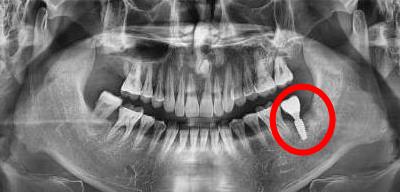

後牙種植牙後拍片